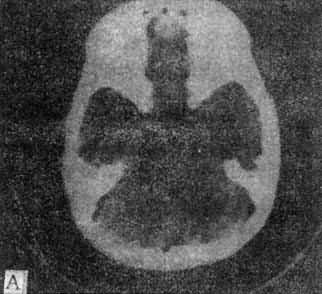

A、蝶鞍一鞍上池层面,鞍上池和后颅凹同时显示,

B、鞍上池层面增强扫描,可见颅底动脉环显形